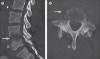

2. CT : Paravertebral soft tissue swelling & abscess, changes in the spinal canal

CT : 척추 감염(Spinal infection)